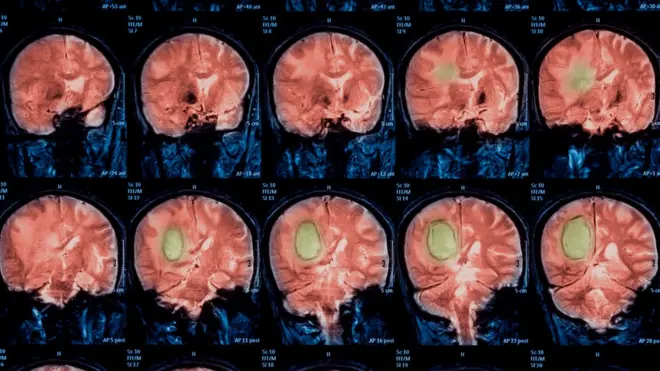

El experimento midió en paralelo la actividad cerebral de los participantes y registró que la reacción de un área conocida como amígdala, en el lóbulo temporal, fue intensa durante el primer engaño.

Con la sucesión de deshonestidades, la actividad en la zona encargada de producirnos un estímulo de incomodidad se debilitaba de manera gradual.

Y mientras mayores las transgresiones, menores las resistencias emocionales.

Pero eso no es todo, a través de la resonancia magnética los científicos lograron predecir los niveles de deshonestidad de los participantes de acuerdo a su actividad cerebral.